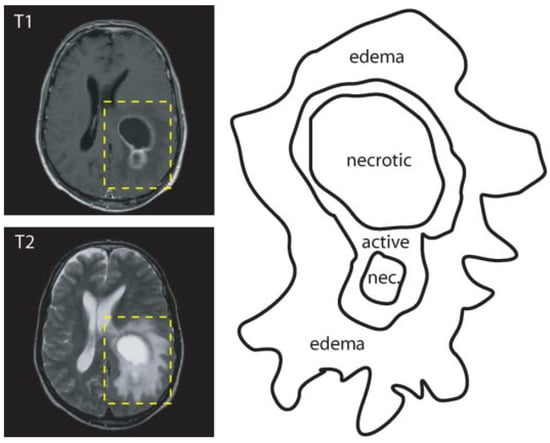

- active tumorous tissue;

- necrotic (dead) tissue; and,

- edema (swelling near the tumor).